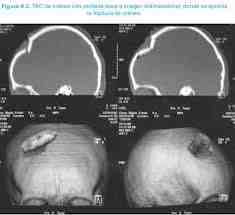

FRACTURA CON HUNDIMIENTO:

FRACTURA HUNDIMIENTO

Es aquella en la que la tabla externa se hunde por debajo del límite anatómico de la tabla interna.

DIAGNÓSTICO: TAC craneal.

TRATAMIENTO: Reparación quirúrgica.